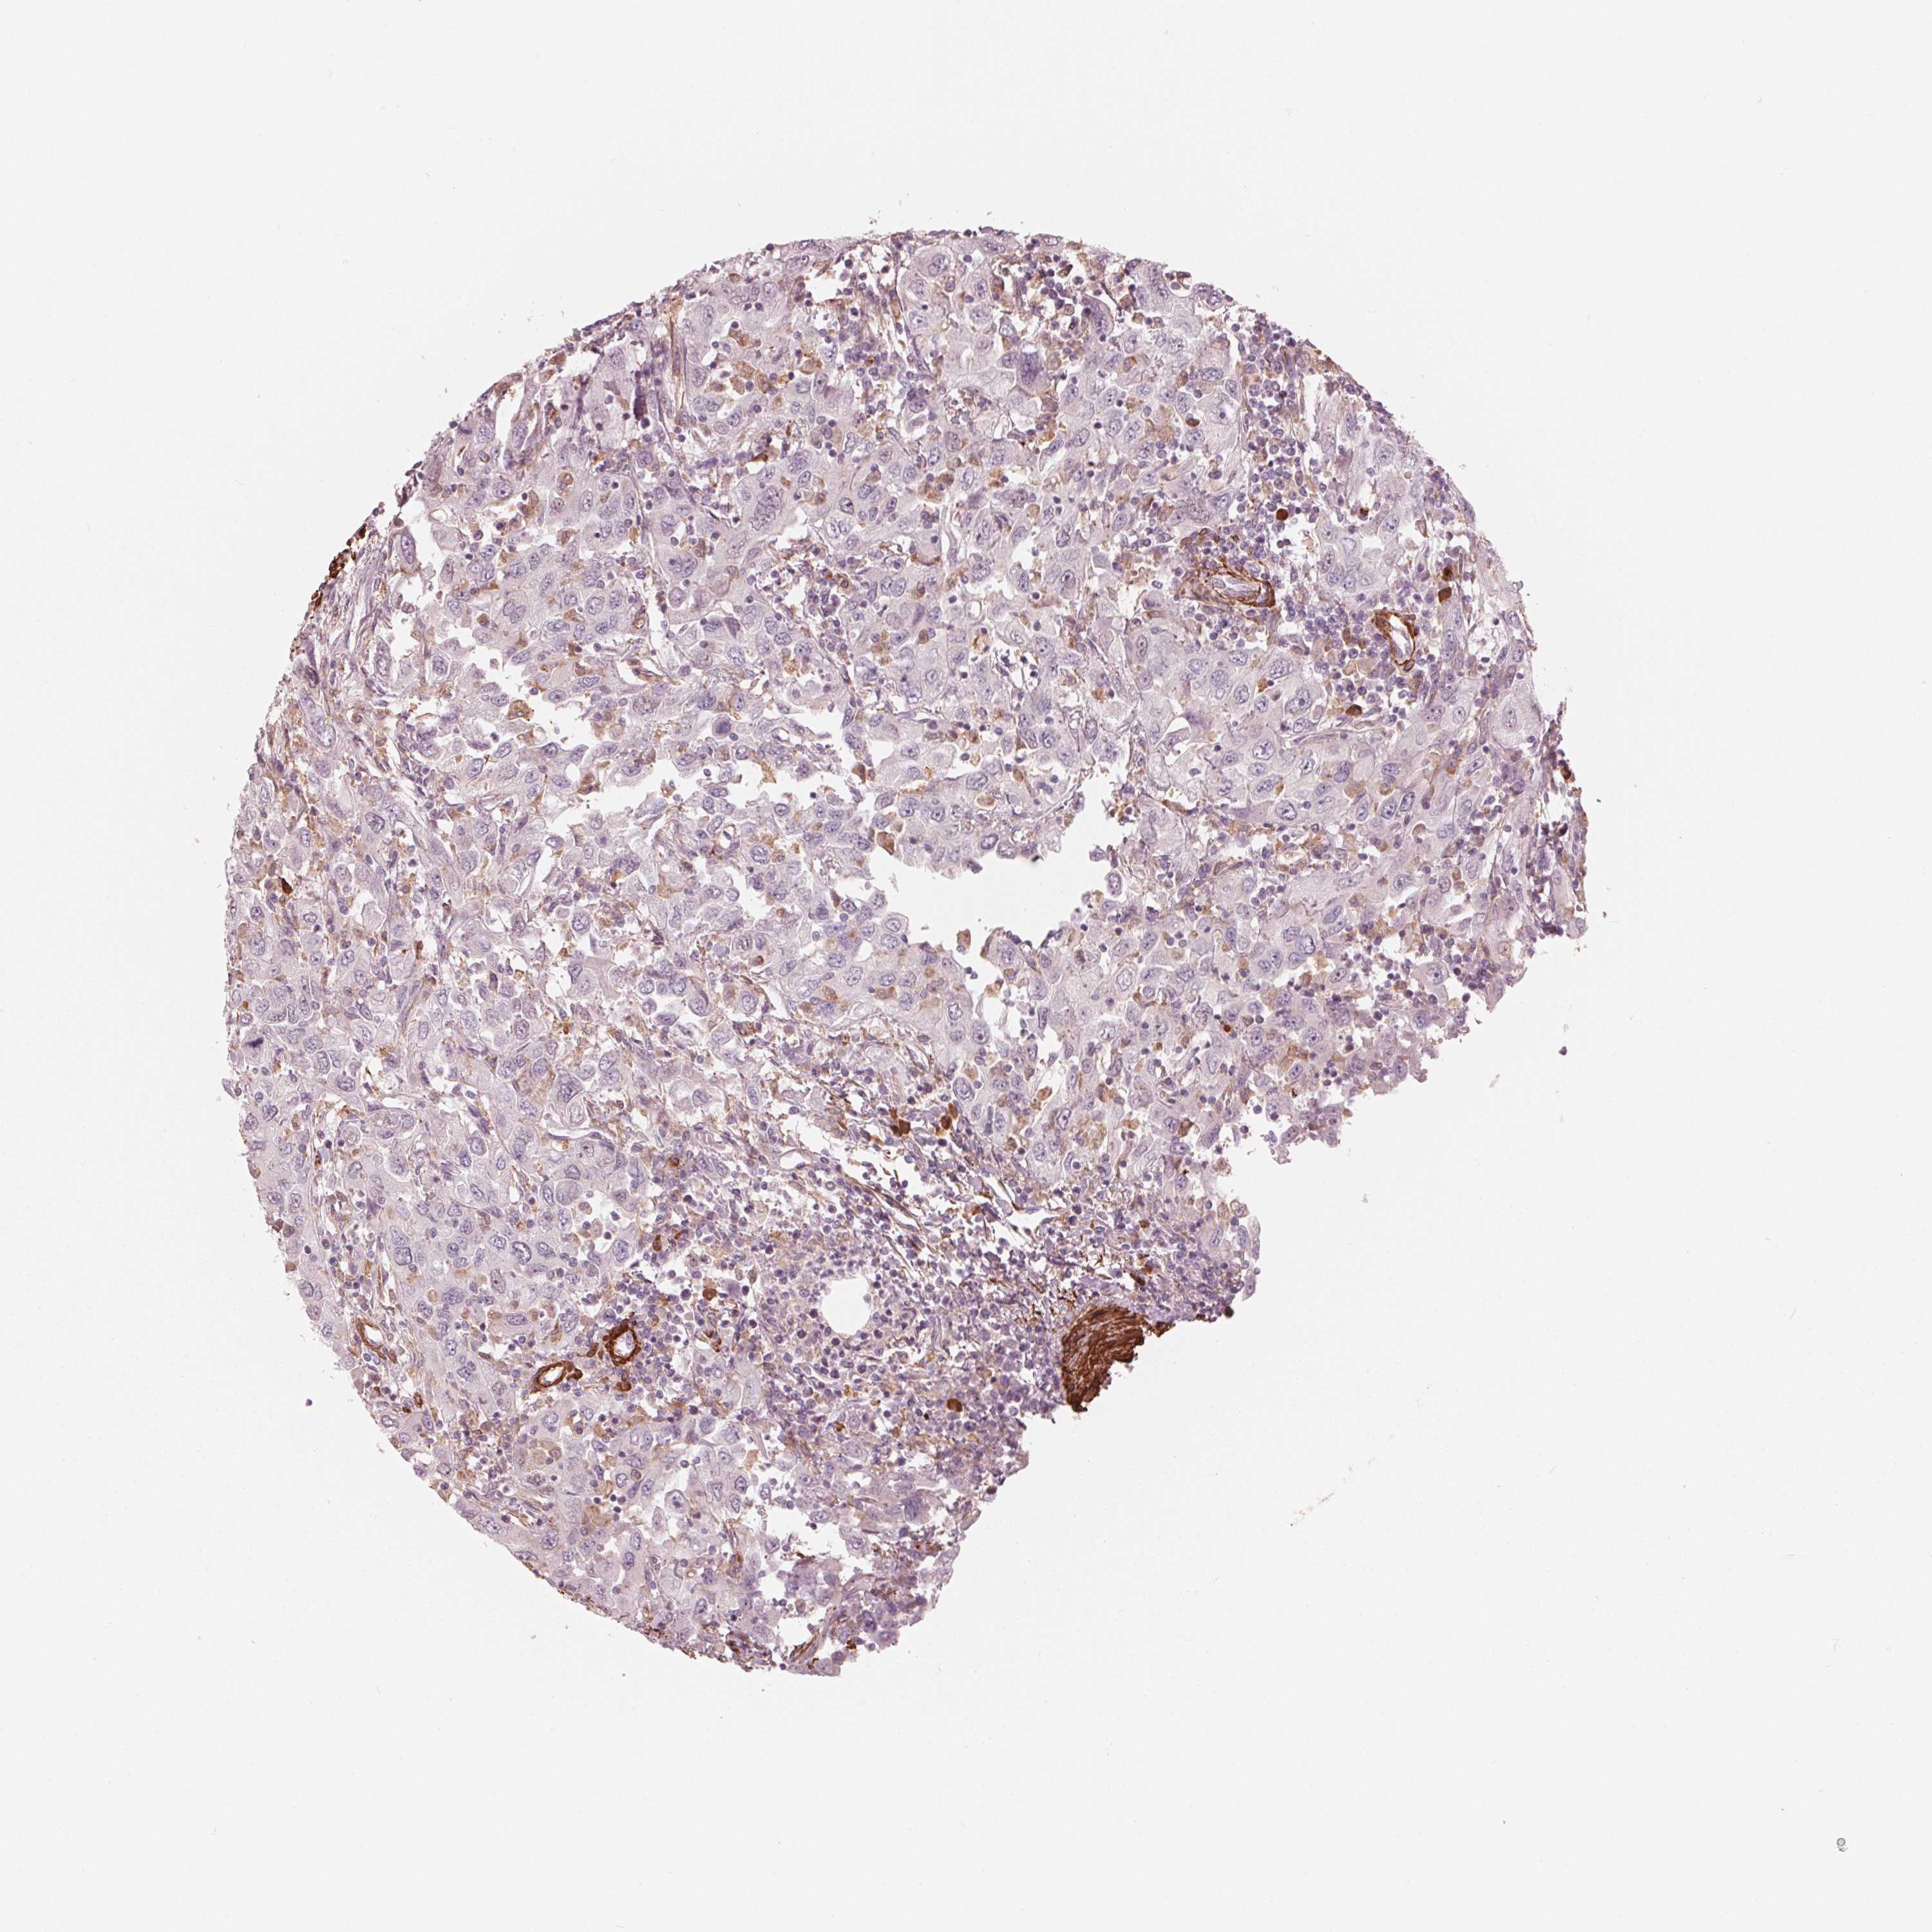

UROTHELIAL CANCER - Protein expressioni

A mouse-over function shows sample information and annotation data. Click on an image to view it in a full screen mode. Samples can be filtered based on level of antibody staining by selecting one or several of the following categories: high, medium, low and not detected. The assay and annotation is described here.

Antibody stainingi

Antibody staining in the annotated cell types in the current human tissue is reported as not detected, low, medium, or high, based on conventional immunohistochemistry profiling in selected tissues. This score is based on the combination of the staining intensity and fraction of stained cells.

Each image is clickable and will lead to virtual microscopy that enables deeper exploration of all samples and also displays staining intensity scores, fraction scores and subcellular localization as well as patient and tissue information for each sample.

Antibody HPA065946

Staining

High

Medium

Low

Not detected

Intensity

Strong

Moderate

Weak

Negative

Quantity

>75%

75%-25%

<25%

None

Location

Nuclear

Cytoplasmic/membranous

Cytoplasmic/membranous,nuclear

Urothelial carcinoma, High grade

Urothelial carcinoma, NOS

Urothelial carcinoma, Low grade